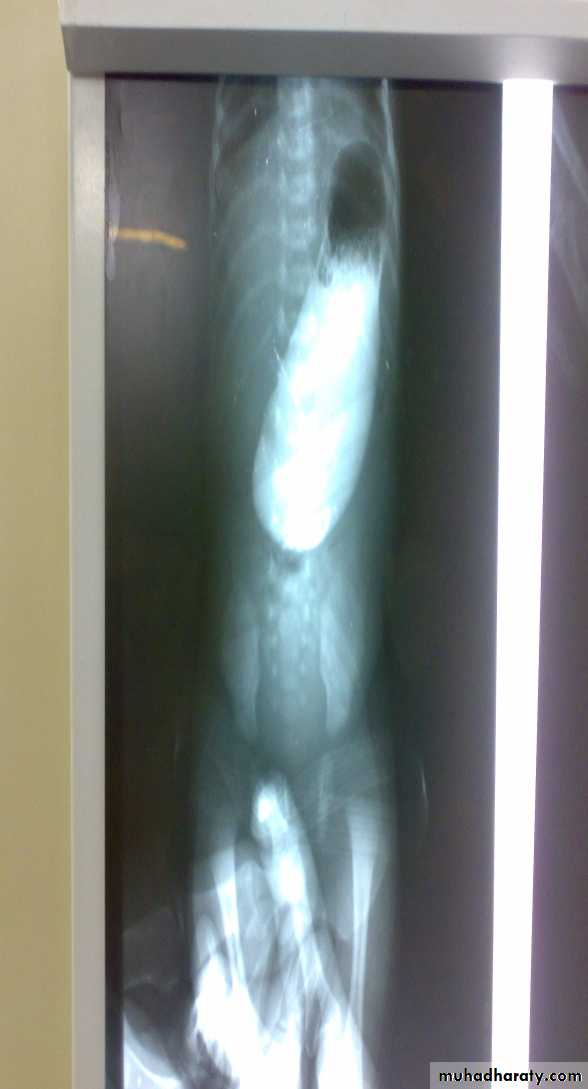

Oesophageal Atresia and Tracheo-Oesophageal Fistula,